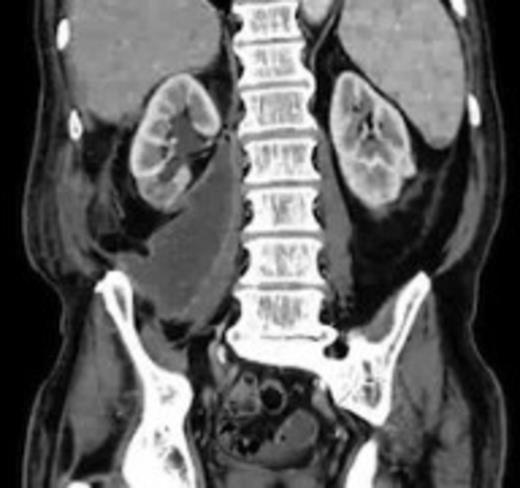

Four weeks following discharge the patient was re-admitted with feeling increasingly unwell, recurrent pyrexia, loss of appetite and mild shortness of breath on exertion. Physical examination was unremarkable except for a temperature of 38.3 centigrade. Blood tests on admission showed Hb 11.4 g/dl (11.5-16.0 g/dl), white cell count 13.1×109/L (4-9.2 x 109/L) and CRP 68mg/L (<3 mg/L). Contrast enhanced CT scan (Fig. 2,3) showed a 50 mm maximum retroperitoneal collection situated between the right kidney and the right iliac vessels. It contained a few loculi of gas. A diagnosis of postoperative right psoas abscess was made. The patient was started on intravenous broad spectrum antibiotics – Tazocin (Piperacillin+ Tazobactam) and Metronidazole. CT guided drainage was carried out using a 10 French gauge pigtail catheter locked pigtail (Meditech Flexima regular all-purpose drainage catheter sets with locking pigtail (Boston Scientific)) (Fig. 4). The isolation of E. coli from the collection with negative Hemocultures suggested a bowel source for the infection but no actual breach was demonstrable. The bowel surgeons ruled out colonic pathology.

A 50 mm maximum retroperitoneal collection situated between the right kidney and the right iliac vessels